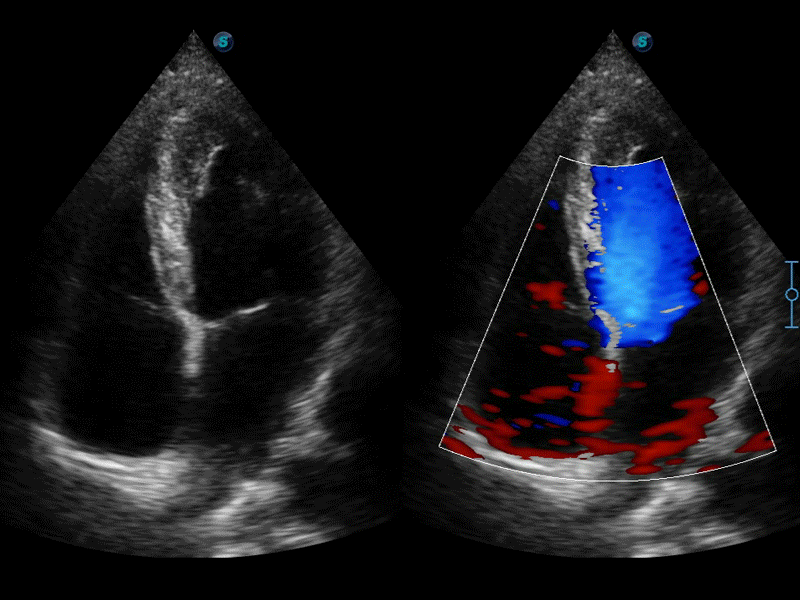

高分辨率血流成像技術(shù)提高了對(duì)低速血流信號(hào)的檢測(cè)能力。在提高空間分辨率的同時(shí),也克服了血流外溢現(xiàn)象,為用戶提供更加真實(shí)的血流動(dòng)力學(xué)信息。